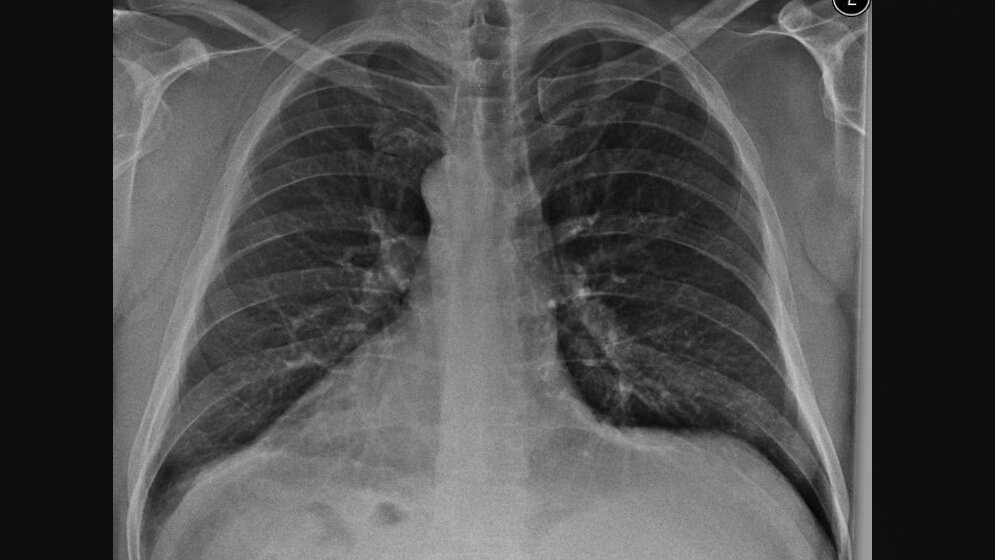

Die Dextrokardie beschreibt ein nach rechts in der Achse gerichtetes Herz. Sie ist vorrangig das Ergebnis einer varianten Entwicklung. Die Dextrokardie kann bei verschiedenen anderen klinischen Veränderungen und im unterschiedlichen Alter der Patienten entdeckt werden.

Dextrocardia is defined as a right-sided heart with a base-apex axis directed rightward. It is resulting from a variation in cardiac development. Dextrocardia can be discovered in various clinical settings and at various patient ages.